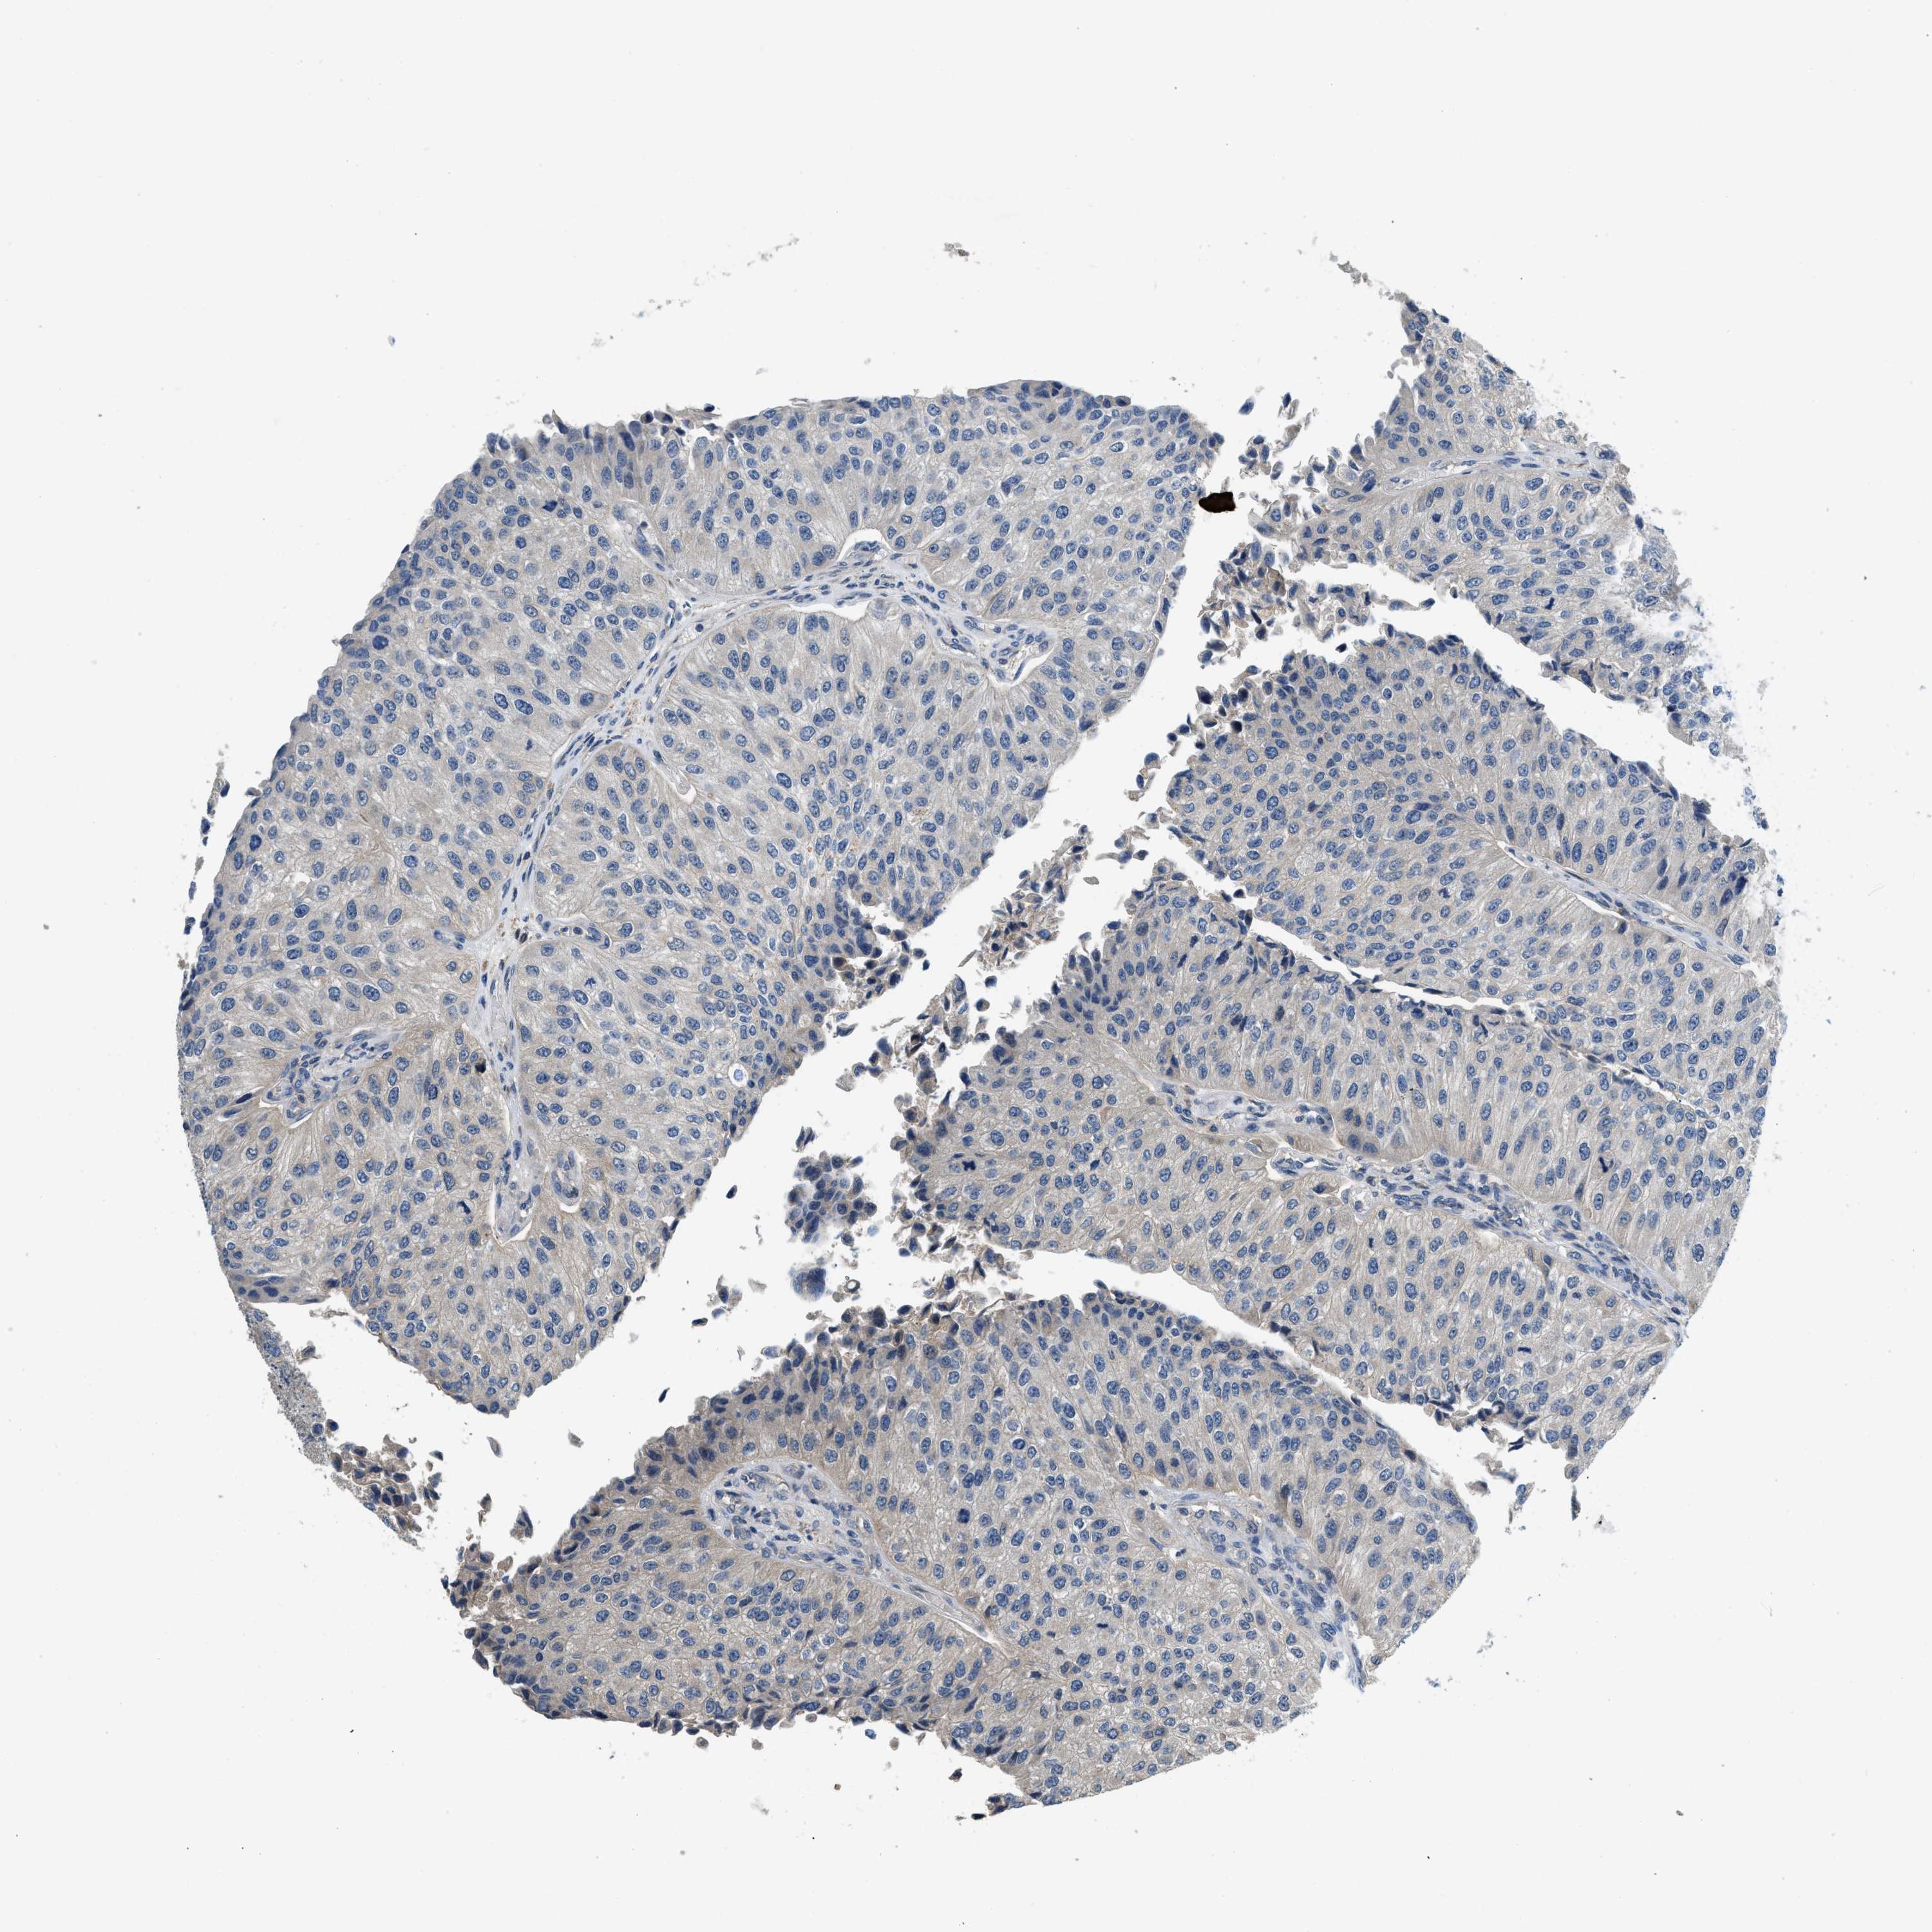

UROTHELIAL CANCER - Protein expressioni

A mouse-over function shows sample information and annotation data. Click on an image to view it in a full screen mode. Samples can be filtered based on level of antibody staining by selecting one or several of the following categories: high, medium, low and not detected. The assay and annotation is described here.

Antibody stainingi

Antibody staining in the annotated cell types in the current human tissue is reported as not detected, low, medium, or high, based on conventional immunohistochemistry profiling in selected tissues. This score is based on the combination of the staining intensity and fraction of stained cells.

Each image is clickable and will lead to virtual microscopy that enables deeper exploration of all samples and also displays staining intensity scores, fraction scores and subcellular localization as well as patient and tissue information for each sample.

Antibody HPA003539

Antibody CAB018374

Urothelial carcinoma, High grade

Urothelial carcinoma, Low grade